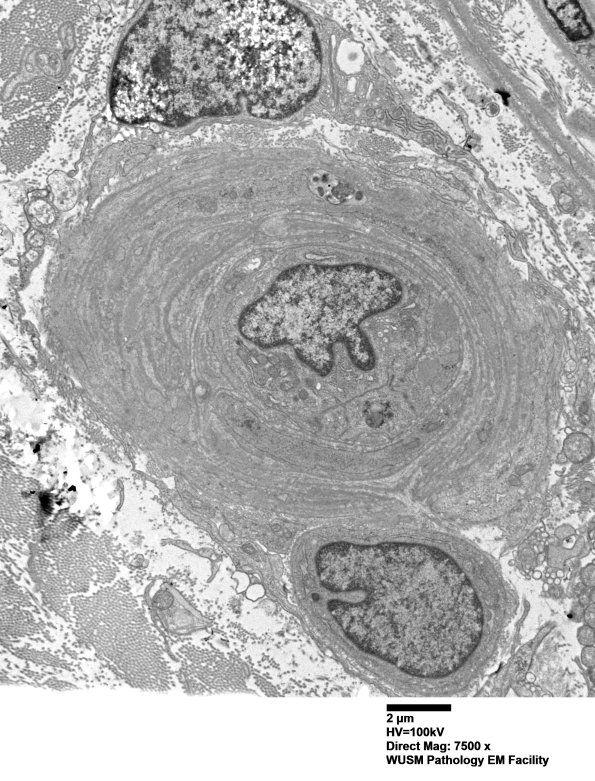

Washington University Experience | VASCULAR | Hypoxia-Ischemia, fetal-neonatal | White Matter | 14B3A (Case 14) EM017 - Copy

14B3A (Case 14) EM017 - Copy